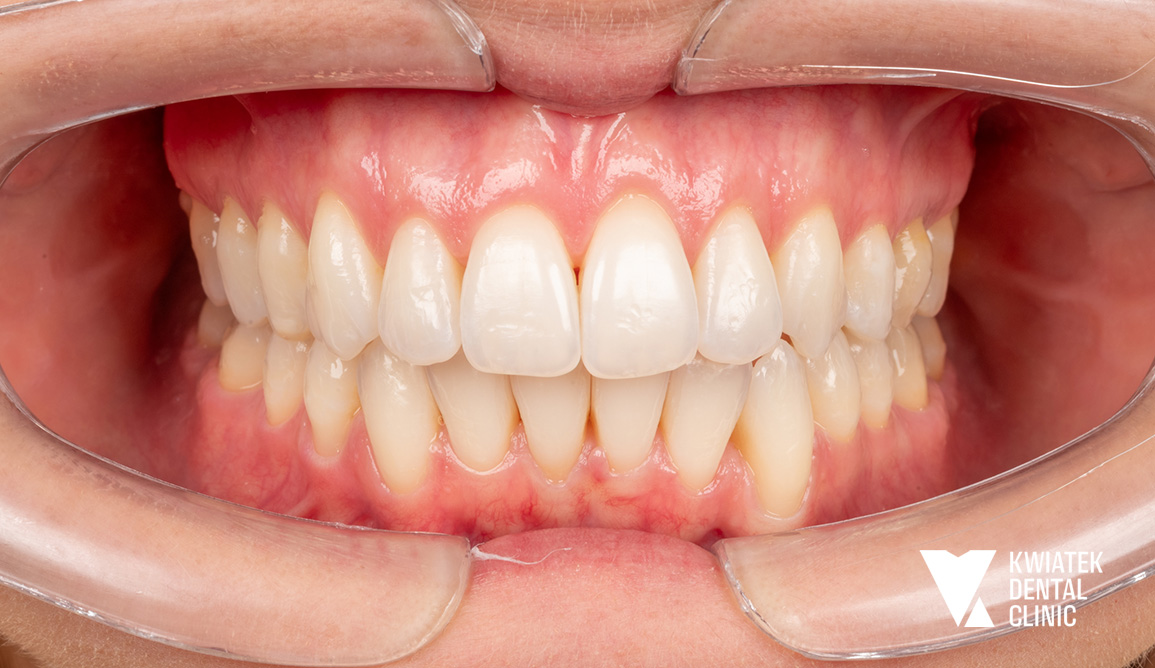

Uśmiech odzyskany – od kompleksowej terapii do naturalnego efektu!

Do naszej kliniki zgłosiła się Pacjentka, która w przeszłości była już leczona ortodontycznie. Mimo wcześniejszego leczenia wciąż zmagała się z brakiem górnej dwójki oraz przesuniętą linią pośrodkową, co wpływało zarówno na estetykę uśmiechu, jak i na prawidłową funkcję zgryzu.

Postawiliśmy na kompleksowe podejście – połączyliśmy leczenie ortodontyczne, implantologiczne oraz protetyczne. Dzięki temu udało się uzyskać harmonijny, pełen blasku uśmiech oraz prawidłowe warunki zgryzowe.

Efekt końcowy? Naturalna estetyka, piękny uśmiech i komfort, który daje Pacjentce pełną satysfakcję.